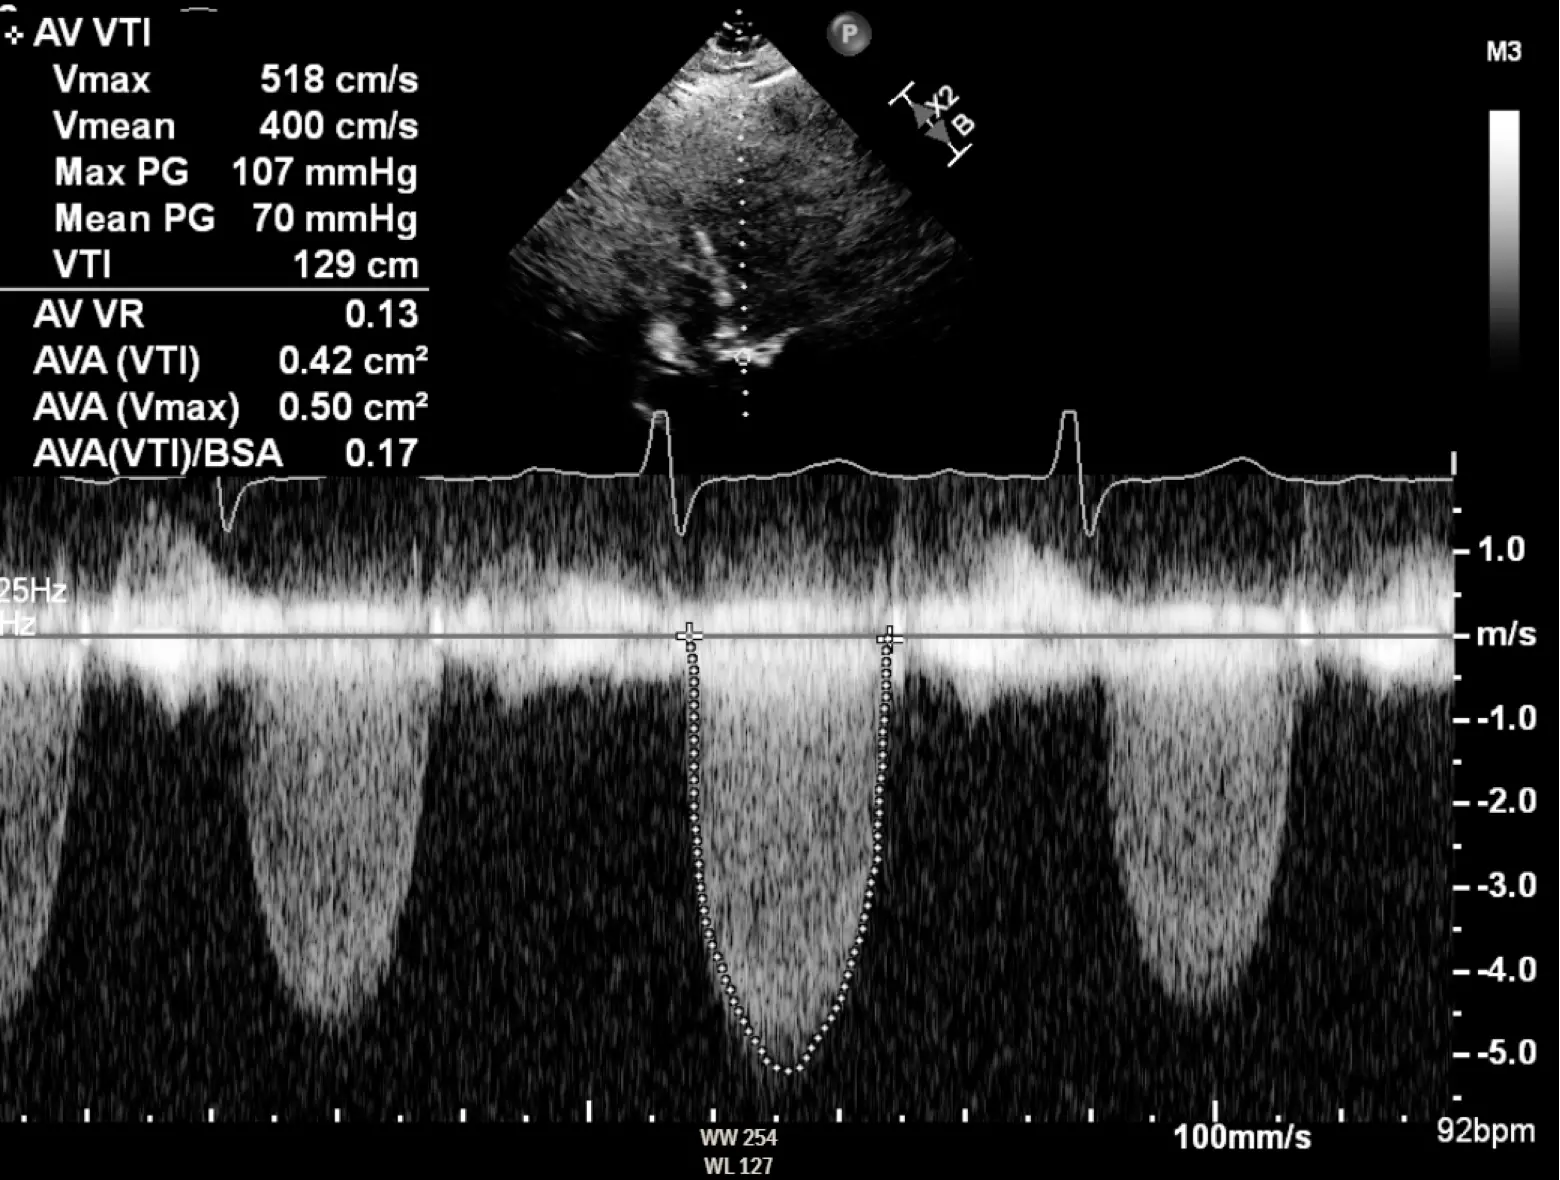

1, 4, 40, and 64

AVA < 1.0 cm2 Peak velocity > 4 m/s Mean gradient > 40 mmHg Peak gradient > 64 mmHg

- ==Valvular AS will be considered severe if mean gradient > 40 mmHg or peak velocity > 4 m/s (regardless of AVA)==

- Aortic velocity is measured using continuous-wave doppler ultrasound with examination from multiple acoustic windows

- Mean gradient is calculated by averaging instantaneous gradients over the systolic ejection period using the modified Bernoulli equation,

- AVA is important, but can be difficult to determine with the continuity equation, which itself is highly operator dependent

- Use if mean gradient < 40 mmHg or peak velocity < 4 m/s

| Aortic sclerosis | Mild AS | Moderate AS | Severe AS | Very Severe AS | |

|---|---|---|---|---|---|

| AVA (cm2) | - | >1.5 | >1.0-1.5 | ≤1.0 | ≤0.60 |

| Mean gradient (mmHg) | - | <20 | 20-40 | >40 | >60 |

| Peak velocity (m/s) | <2.0 m/s | 2.0-2.9 | 3.0-3.9 | ≥4.0 | ≥5.0 |

| Indexed AVA (cm2/m2) | >0.85 | >0.60-0.85 | ≤0.6 | ||

| Velocity ratio | >0.50 | >0.25-0.50 | ≤0.25 |

- The above figure is from the Mayo Echo Boards video where the presenter highlights the importance of calculating the AV TVI in multiple windows to ensure you are appropriately calculating the highest VTI and avoid miscalculation/miscalssification. In Thaden et al (JASE, 2015), the authors found that peak velocity was found outside of the apical window 61% of the time and that neglecting non-apical window misclassified AS 23% of the time.